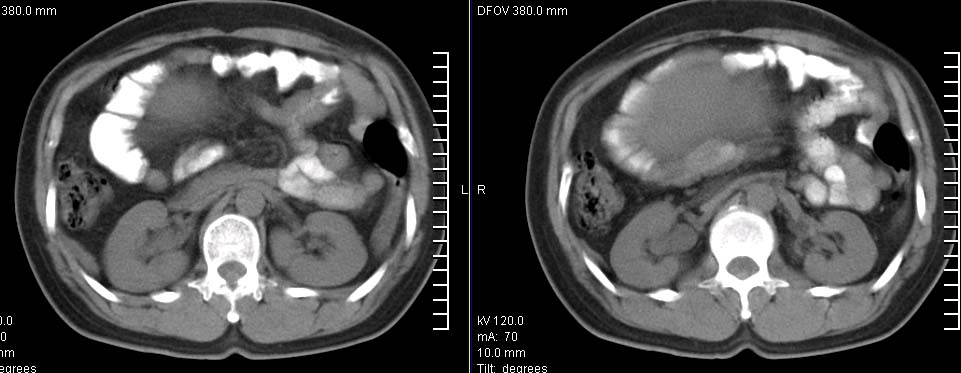

标题: CT9722:卵巢巨大占位,约10*18*21CM大小 [打印本页]

标题: CT9722:卵巢巨大占位,约10*18*21CM大小

卵巢巨大占位,约10*18*21cm大小

卵巢囊腺瘤可能性大.可见低密度

考虑:右侧卵巢囊性瘤可能性大 建议增强扫描。

肿瘤的密度有点高.和子宫差不多?且和子宫相连呢?我考虑来源于子宫,子宫巨大子宫肌瘤可能性大!(局部有坏死?)

右侧卵巢囊性瘤可能性大 ,5楼,密度不一样,是窗调得太宽

囊腺瘤不管是浆液性,还是黏液性的,液体成分应该占的比例很大吧!!这个病灶其实是个实性肿块,更看不到囊腺瘤所能见到的分隔??请笔者提供ct值?望大家再仔细分析??

右侧附件区巨大囊性肿块,边缘光滑,密度较高,左侧缘由多个低密度区,首先考虑囊腺瘤可能。